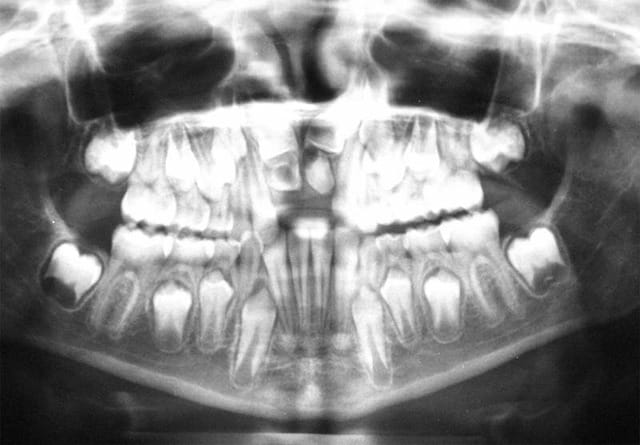

Pourquoi la 11 est elle descendue et pas la 22 ?

sur la Rx. avant Chir., on voit que la 22 est en position plus apicale que la 21

voici une Rx. après Chir., ou on voit que le dégagement osseux de la 22 est moins important que sur la 21, sans doute à cause de sa position plus apicale

ce qui expliquerait pourquoi la 22 est restée bloquée

@+ Bjc.